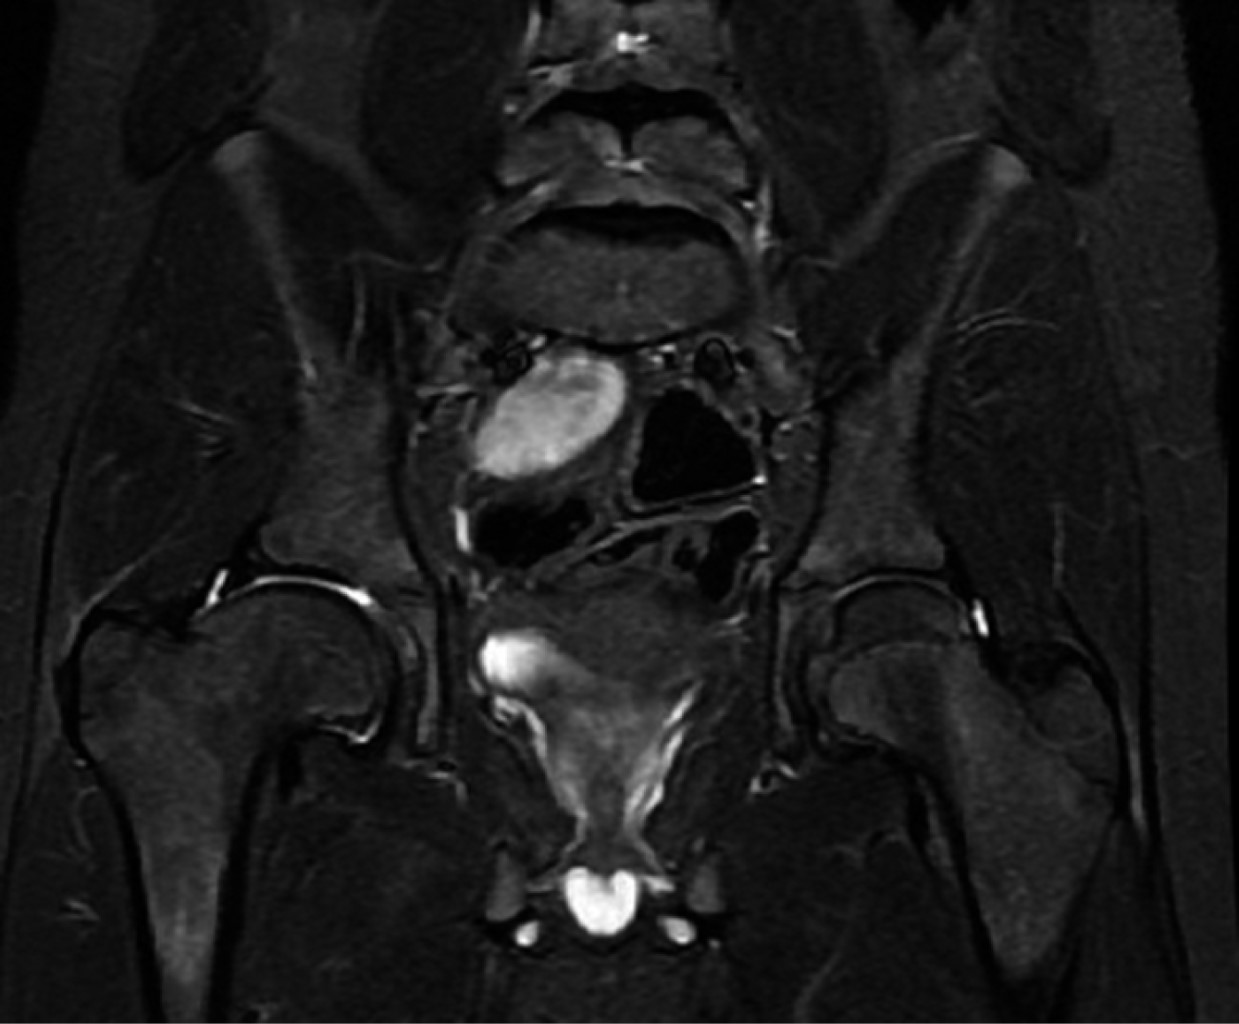

Treatment of femoroacetabular impingement with controlled dislocation of the hip

The femoroacetabular impingement is a syndrome caused by abnormal contact between the femoral head and the acetabulum; it can progress in complications, and the treatment must be individualized with the aim to restore the functionality of the joint. A case of a 12 years old patient who presented clinical findings about impingement, he has history Perthes disease. We performed a surgical hip dislocation technique with femoroplasty. We obtained good results. The clinical and radiographic characteristics of the patient has described and the case resolution.

Figure 1